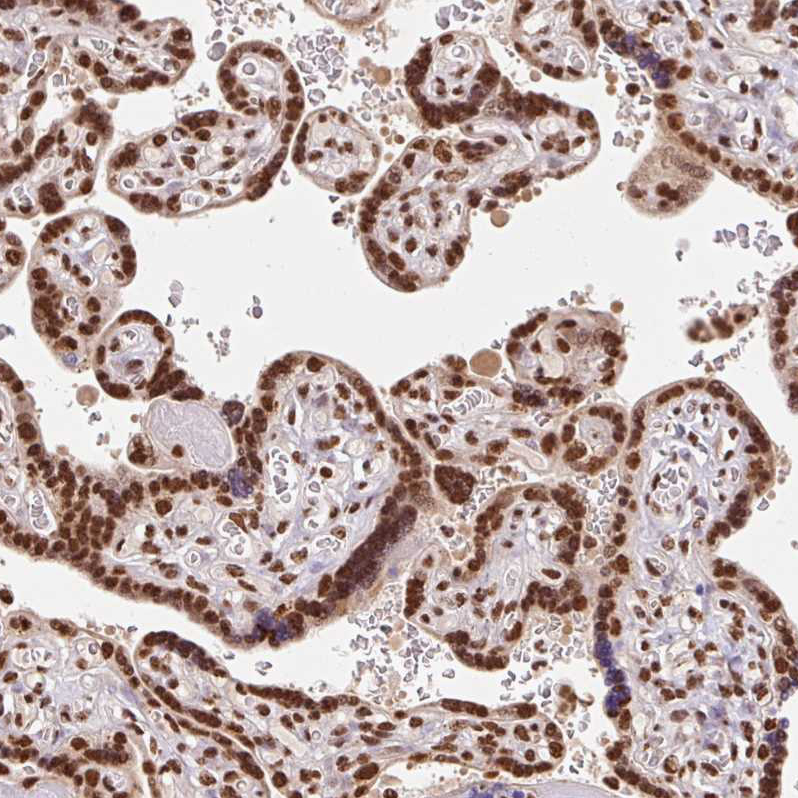

Immunohistochemical staining of human placenta shows strong nuclear positivity in trophoblastic cells.